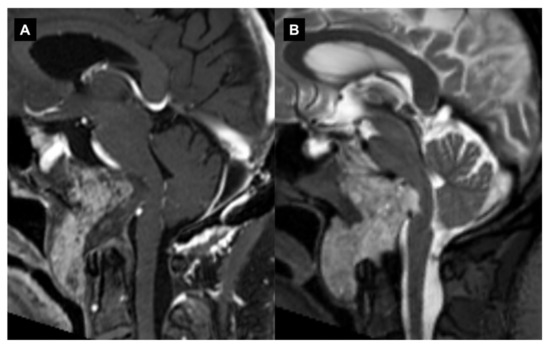

However, one of the potential complications of the transclival–transodontoid EEA is the postoperative instability of the CVJ (Figure 5).

Figure 5.

Endoscopic endonasal approach to CVJ chordoma and occipitocervical fixation. Sagittal preoperative (A) and postoperative (B) T1-weighted MR images after contrast injection showing the chordoma infiltration of C0-C1-C2 complex joint and a gross total resection. In the same surgical setting, an occipitocervical fixation was performed. A 3D reconstruction of the postoperative CT (C).

This can occur when the stability of the CVJ is compromised by the surgical procedure or preoperatively by tumor growth, which leads to symptoms such as neck pain, weakness and spinal cord compression. The risk of postoperative instability can be reduced by careful preoperative planning, proper surgical techniques and appropriate postoperative management [107]. There are several different techniques that have been used to prevent instability after the EEA. These include the use of internal fixation devices such as screws and rods in the pre- or immediate postoperative course, as well as the use of external fixation devices such as halo traction. There have been several studies published in recent years that have investigated the incidence and management of postoperative instability after applying the EEA for CVJ tumors, with a focus on condyle resection. An anatomical study showed that a lower-third clivectomy and unilateral anterior condylectomy through an EEA can cause progressive hypermobility at the CVJ. On the basis of biomechanical criteria, OCF is indicated for patients who undergo a > 75% anterior condylectomy [108]. Kooshkabadi et al. evaluated the incidence of postoperative instability after an EEA for CVJ tumors. The study included 212 patients who underwent an EEA for lower clivus lesions, and they found that around 3.3% of the patients required a fixation. They showed that an EEA resection greater than 75% of the occipital condyle significantly increased the risk of CVJ instability, which required subsequent fixation. The degree of the condyle resection was a significant factor that predisposed it to the occipitocervical instability [109]. There are also some reports, mainly related to the EEA to CVJ abnormalities and basilar invagination, on the preservation of the anterior C1 arch that avoids the need for posterior fixation with the aim of preserving the rotational movement at the C0–C2 segment and reducing the risk of a subaxial instability development [98,110,111]. Overall, these studies suggest that the entity of condyle resections, C1 anterior arch and transverse ligament preservation while using the EEA on CVJ tumors may represent two significant factors that are related to the risk of postoperative instability [107,112]. However, the evidence is not entirely consistent, and further studies with larger patient populations and longer follow-ups are needed to better understand the risk. The most consistent risk factor identified across these studies is the size and location of the tumors, specifically tumors located in the upper cervical spine and tumors with a wide base. Other factors that have been identified as risk factors for postoperative instability include the degree of resection, the surgical approach and the reconstruction methods used.